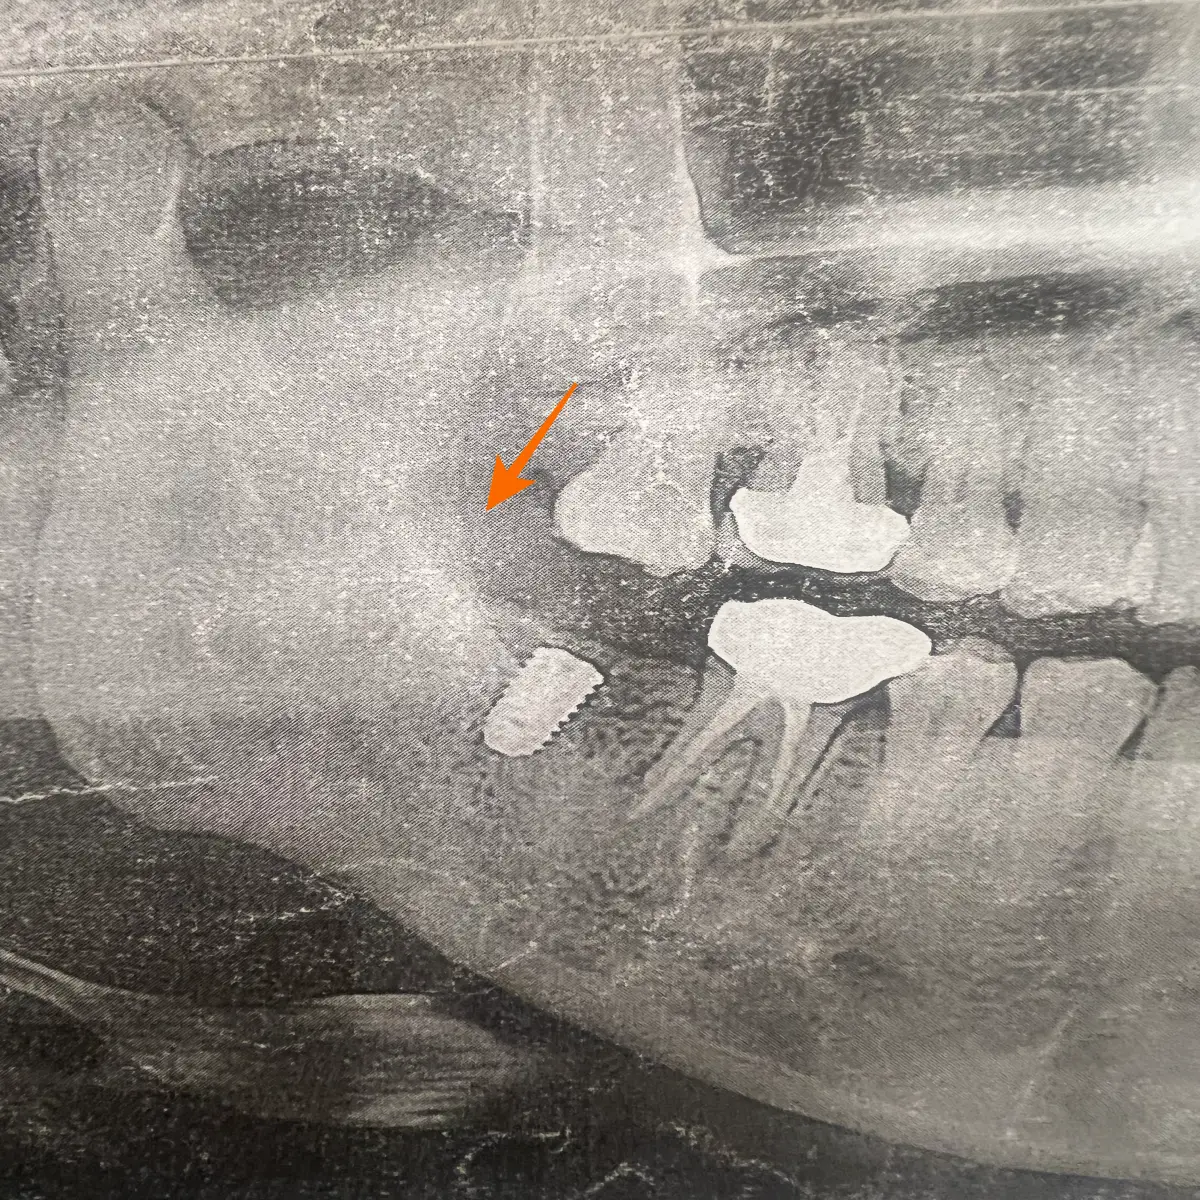

아래 치아, 위 치아가 높이가 안 맞으면 부정 교합이 일어난다고 해요. 저는 아래 맨 끝 어금니 발치 후 5년이나 방치해서 위 치아가 많이 내려온 상황이었어요.

아래-어금니를-발치하고-그-자리-위에-있는-어금니가-내려앉은-모습의-사진

그래서 처음 치과에 갔을 때 들은 얘기가 임플란트하면 내려온 위 치아와 교합이 안 맞아서 위 치아를 좀 많이 깎아야 하는데 그러면 신경치료를 해야 하고 신경치료를 하면 치아가 약해져서 치아 보철물을 씌워야 한다는 것이었어요.